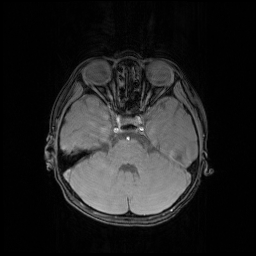

We evaluate the proposed DECN framework using PSNR and SSIM (structural similarity index) [30] as quantitative image quality assessment measures. We give the quantitative reconstruction results of all the test data on different under-sampling patterns and different under-sampling ratios in Table II. We show the Cartesian 30%percent3030\% under-sampling mask in Figure 6(b) and the Random 20%percent2020\% under-sampling mask in Figure 7(b). We observe that DECN improved all off-the-shelf CS-MRI inversion methods on all the under-sampling patterns. Since the Random mask enjoys the more incoherence than the Cartesian mask with the same under-sampling ratio, the CS-MRI achieves better reconstruction quality on the Random masks. Also, we observe the plain DC-CNN model already achieves good reconstruction accuracy, leaving less structural errors for the error correction module, leading to the limited performance improvement about 0.1 dB on the Random 20%percent2020\% and 30%percent3030\% masks. While for other CS-MRI inversions on various sampling patterns, the improvements are at least 1.5dB or even up to 3.5 dB.

In Figure 7, we also compare the MR images produced by the TLMRI, PANO and GBRWT with their DECN counterparts on the 2D 20%percent2020\% under-sampling mask. The subjective comparison DC-CNN and DE-CNN-DECN isn’t included because of the limited improvement. The results are consistent with our observation in Cartesian under-sampling case.

Refer to caption

(a) Fully-sampled

(b) 2D 20%percent2020\% Mask

(c) Zero-filled

(d) Full-sampled

(e) Full-sampled

(f) Full-sampled

(g) TLMRI

(h) PANO

(i) GBRWT

(j) TLMRI-DECN

(k) PANO-DECN

(l) GBRWT-DECN

(m) ΔΔ\Delta TLMRI

(n) ΔΔ\Delta PANO

(o) ΔΔ\Delta GBRWT

(p) ΔΔ\Delta TLMRI-DECN

(q) ΔΔ\Delta PANO-DECN

(r) ΔΔ\Delta GBRWT-DECN

Figure 7: We show the reconstruction results of our DECN framework on TLMRI, PANO and GBRWT methods with local area magnification on Random 20%percent2020\% under-sampling mask. We also show the reconstruction error for our DECN model under different guide module in the last row.